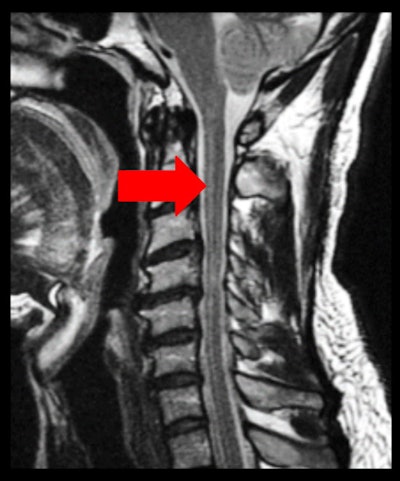

The Gibbs ringing, or truncation, artifact is caused when using a too-small acquisition matrix, which generates an error of the Fourier transform. The solution is to repeat the scan with a larger phase-encoded matrix, a larger acquisition matrix, or a smaller FOV. The phase-encoding matrix should never be less than half of the frequency-encoded matrix, they noted.

The Gibbs ringing effect. Sagittal T2-weighted image of cervical spine. Parallel bands-like areas of alternating high and low signal intensity occur at sharp transition edges of an object – in this case, the cerebrospinal fluid and the medulla (arrow).The Zipper effect artifact is caused by external RF emission finding its way into the magnet room and being picked up by the receiving coils. This may be due to a break in the Faraday cage or the metallic shield built into the walls, floor, and ceiling of the scanning room. It appears as a line of alternating light and dark pixels, sometimes two or three pixels wide, extending across the image in the phase-encoded direction.